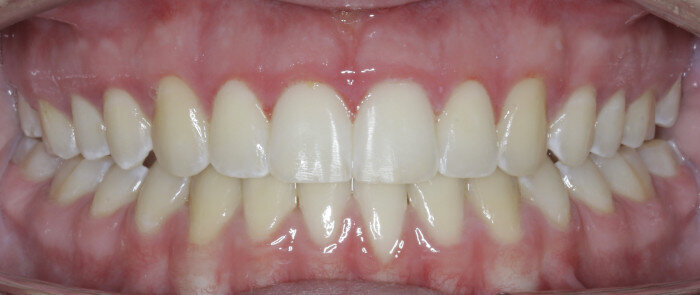

Example 1:

The anterior gummy smile The anterior gummy smile is one in which the patient shows excess gingival display from maxillary canine to maxillary canine (Figs. 4 & 5, beginning of treatment). This takes into account the ideal crown shape and size, where the patient has true anterior maxillary excess and is not just in need of a gingivectomy or crown lengthening procedure. To best determine if gummy smile treatment is needed in the anterior, the authentic smile photograph is used, alongside measurement of the incisor display at rest. If the resting incisor display is greater than threequarters in the adult patient without altered passive eruption, gummy smile treatment is needed. These cases are treated using two TADs placed between tooth #13 and #12 or between #22 and #23 using a 1.6 × 6.0 mm TAD. If slight posterior impaction is desired, bite turbos with Triad Gel (Dentsply Sirona) are placed on teeth #37 and #47 and squeezing exercises used to impact posterior molars engaging the posterior fibres of the temporal muscles (60 squeezes six times per day).

Fig. 4

Fig. 5